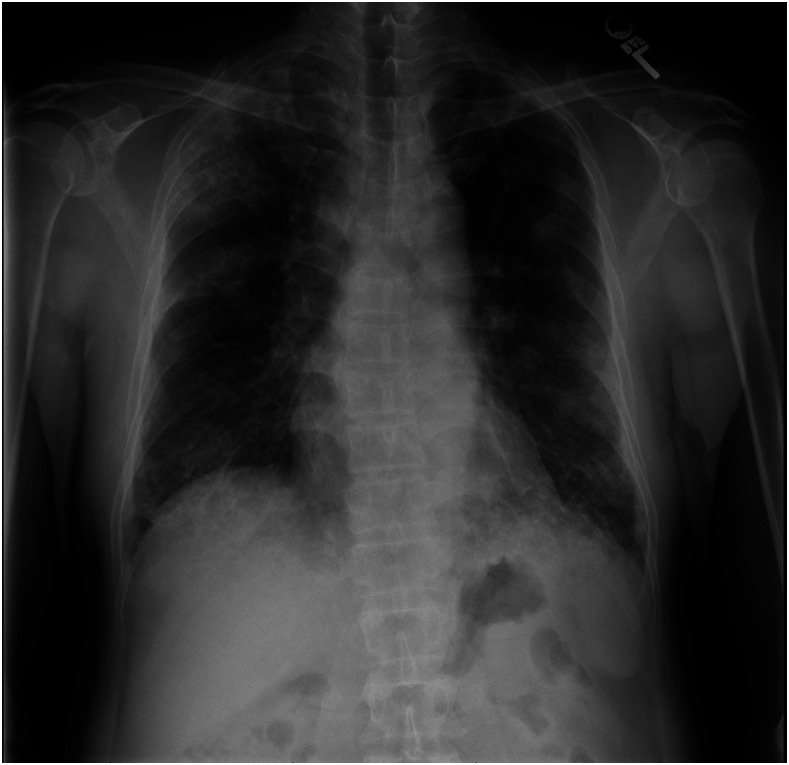

On presentation, the patient was in no acute distress. He was afebrile. Oxygen saturation was 94% on room air. Pulmonary examination was normal. His laboratory findings revealed a white blood cell (WBC) count of 11.5 cells × 109/L with 1.7% eosinophils (absolute eosinophil count of 0.2 cells × 109/L). Liver enzymes were normal. Chest X-ray showed bilateral airspace opacities, with focal consolidation in the right upper lobe and at the bases (Figure 1). Computed tomography of the chest with contrast showed multifocal reticular and ground-glass opacities, an 11-mm spiculated nodular mass within the left apex, and associated bulky mediastinal and hilar lymphadenopathy (Figure 2).

Figure 1.

Chest X-ray. Initial chest X-ray showed bilateral airspace opacities with focal consolidation in the right upper lobe and at lung bases.